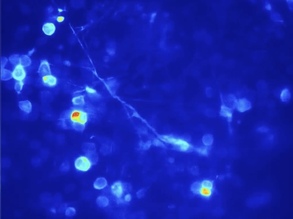

Busybody...Fitter Brain